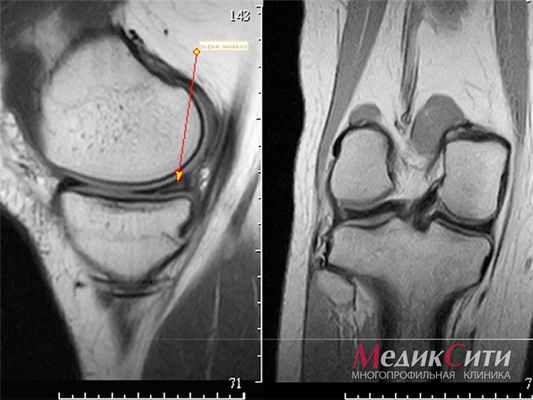

- данные УЗИ либо МРТ суставов (если это необходимо врачу на ранней стадии заболевания);

- рентгенография кистей и стоп. Характерные для ревматоидного артрита эрозивные изменения развиваются в первую очередь в этих суставах, но не ранее 6 месяцев. Для отслеживания состояния легких и сердца делается рентгенография органов грудной клетки, по особым показаниям – компьютерная томография легких. МРТ или УЗИ - особенно если заболевание находится на начальном этапе, когда внешняя деформация суставов не так заметна, и важно отследить незначительные изменения.